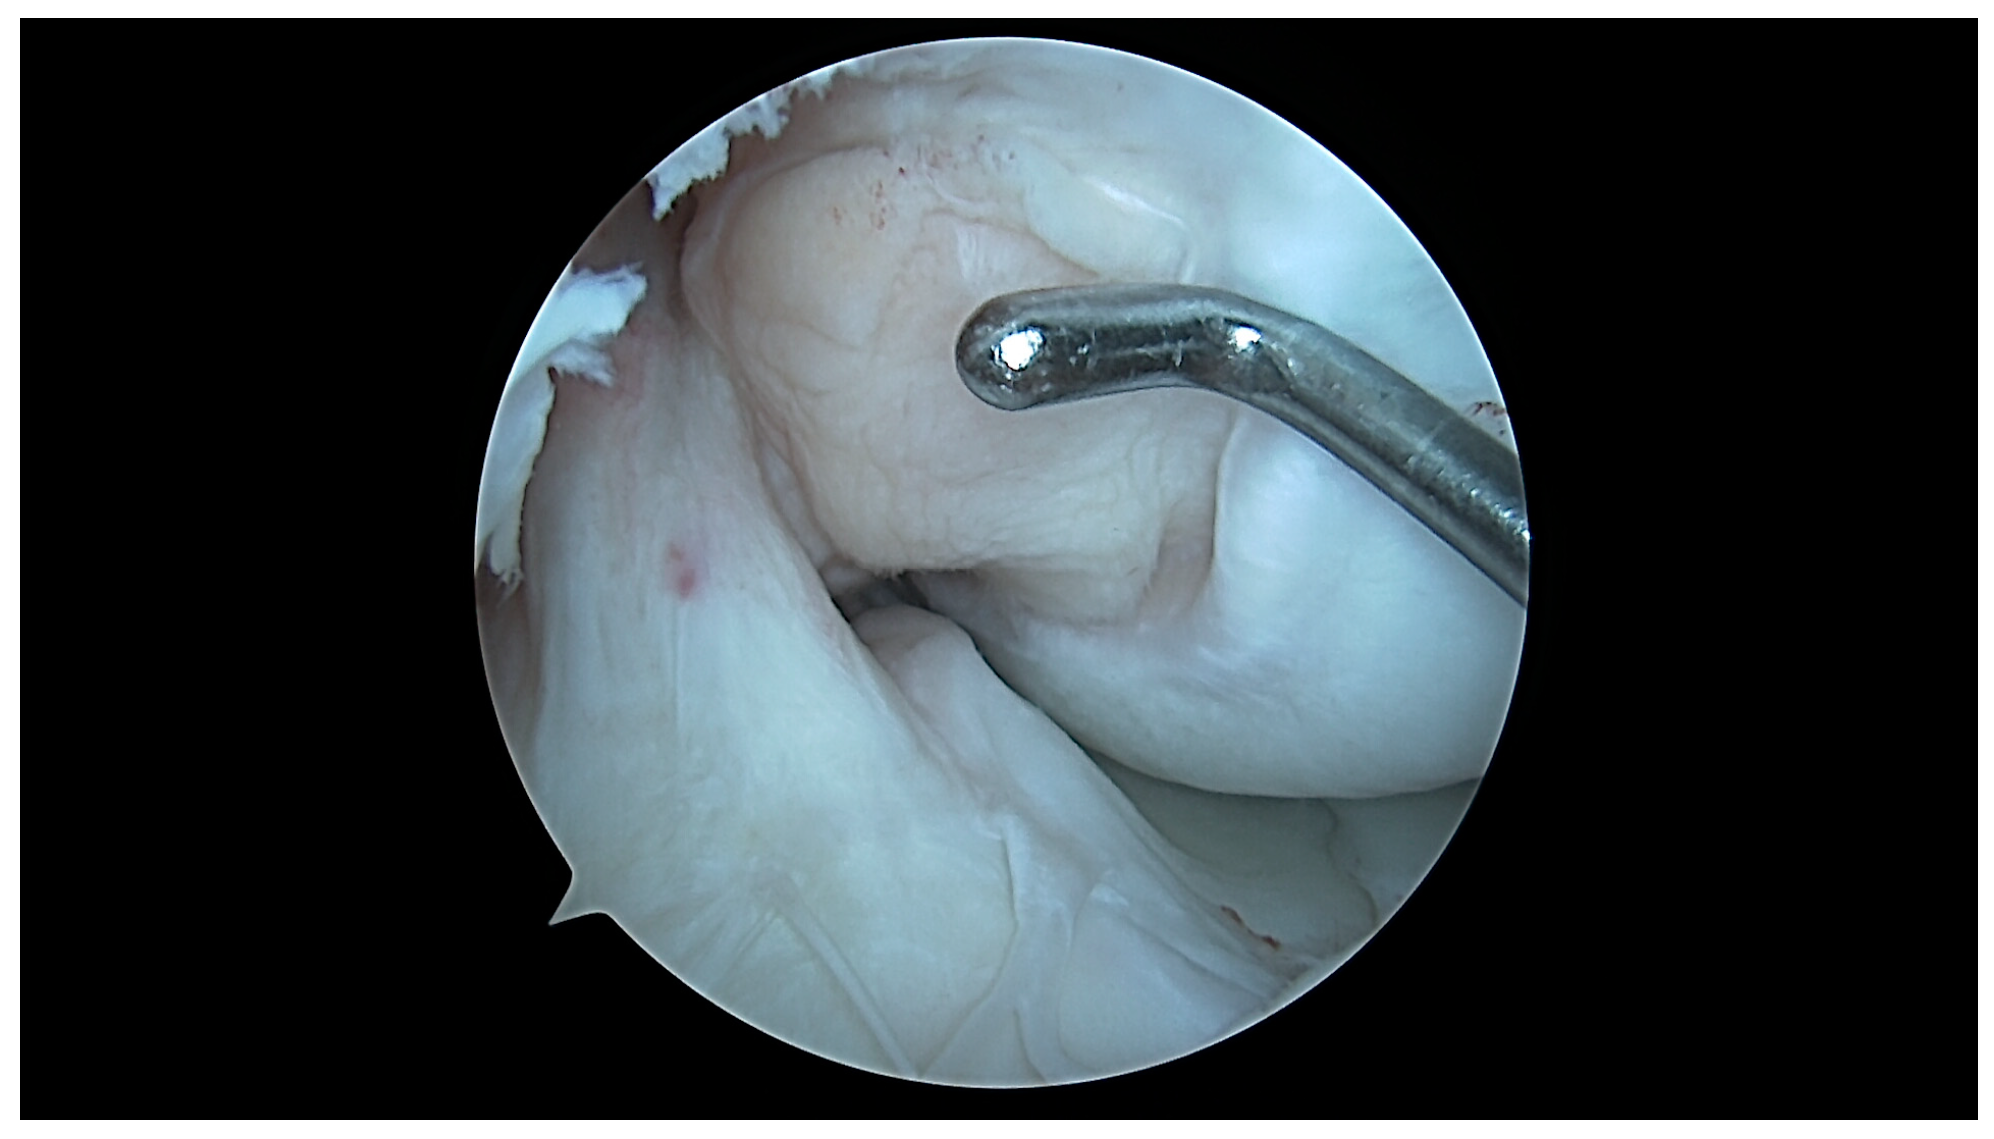

4.1. U-Shaped Notch

4.2. A/W Shaped Notch